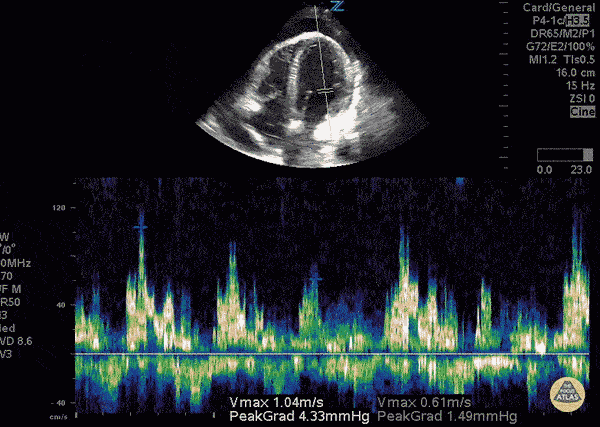

Mitral inflow velocity respiratory variation > 25% consistent with cardiac tamponade physiology. Sukh Singh, MD